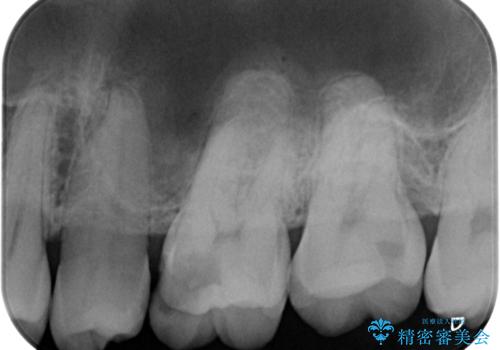

- 歯が欠けたとのことで来院された患者様です。

1本はゴールドアンレー、もう1本はセラミックインレーで修復します。

- 左上6/ゴールドアンレー:110,000円 左上7/セラミックインレー:77,000円費用は治療当時の料金となります

患者様の咬む力や削るべき歯の量によって、使用する材料を決めております。